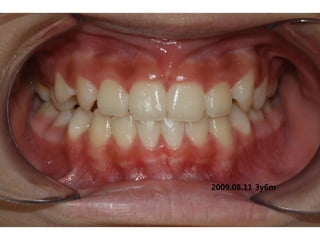

1999.04.05/F

C.C

• Diastema, flattened lower ant.

Dx

• Mentalis action, heavy labial frenum

Goal

• Establish normal lip tone

2006.02.08

2004.05.13

2006.12.27 10m

2007.05.08 1y 3m

2008.07.30 2y 5m

2009. 02.18.3y

2009.08.11 3y6m

2010.06.15 4y4m

2012 02 01

out of Tr 2yr